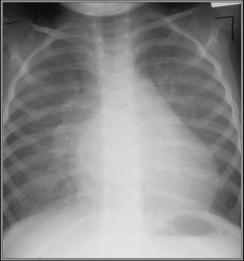

Congenital Mitral Stenosis